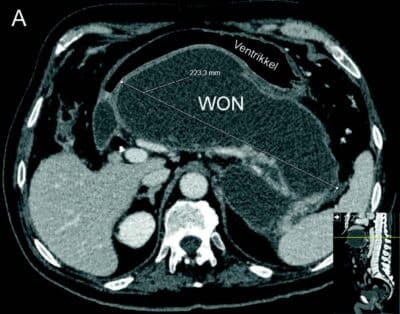

Endoskopisk behandling er som nevnt førstelinjebehandling og bør uansett forsøkes først dersom teknisk mulig da ekstern drenasje av væskefasen og eventuell tilførsel av luft i WON kan vanskeliggjøre senere endoskopisk behandling. Tilhelingstid er normalt 4-6 uker avhengig av størrelse, utbredelse og andel faste nekroser i kaviteten, men kan hos enkelte pasienter være betydelig lenger. Stenten (LAMS) fjernes når kaviteten er borte (Fig 2).

- Fig 2: CT bilder fra pasient med nekrotiserende pankreatitt og behandlingstrengende WON før drenasje (A) og 4 uker etter (B) innleggelse av LAMS (pil).